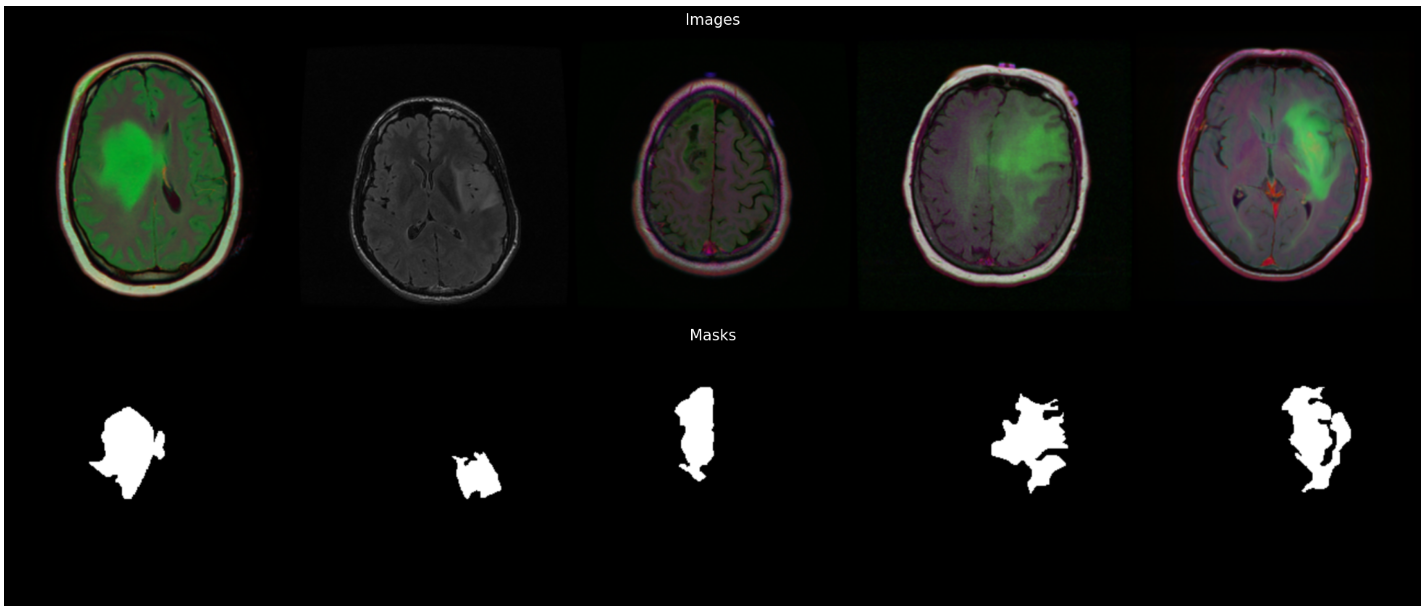

基于深度学习的MRI分割提取LGG的多维度形状特征

大家好,我是带我去滑雪! 随着精准医疗和个体化治疗的快速发展,传统的组织学分型已逐渐无法满足对脑胶质瘤这一复杂疾病的深度理解。低级别胶质瘤(Low-Grade Glioma, LGG)是一种生长缓慢但潜在恶性的脑部肿瘤࿰…